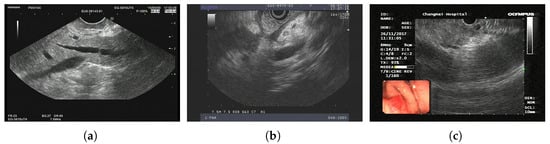

As shown in Figure 3, ITK-SNAP [] was used to visualize CT images, where the red labels represent healthy pancreatic tissues and the green parts represent PC tissues. The task of this dataset is to subdivide the pancreas and the PC, the latter being relatively challenging.

Figure 3.

MSD sample data pancreas_004.nii.gz: (a) 3D visualization of pancreas and PC, (b) main view, (c) left view, and (d) top view.